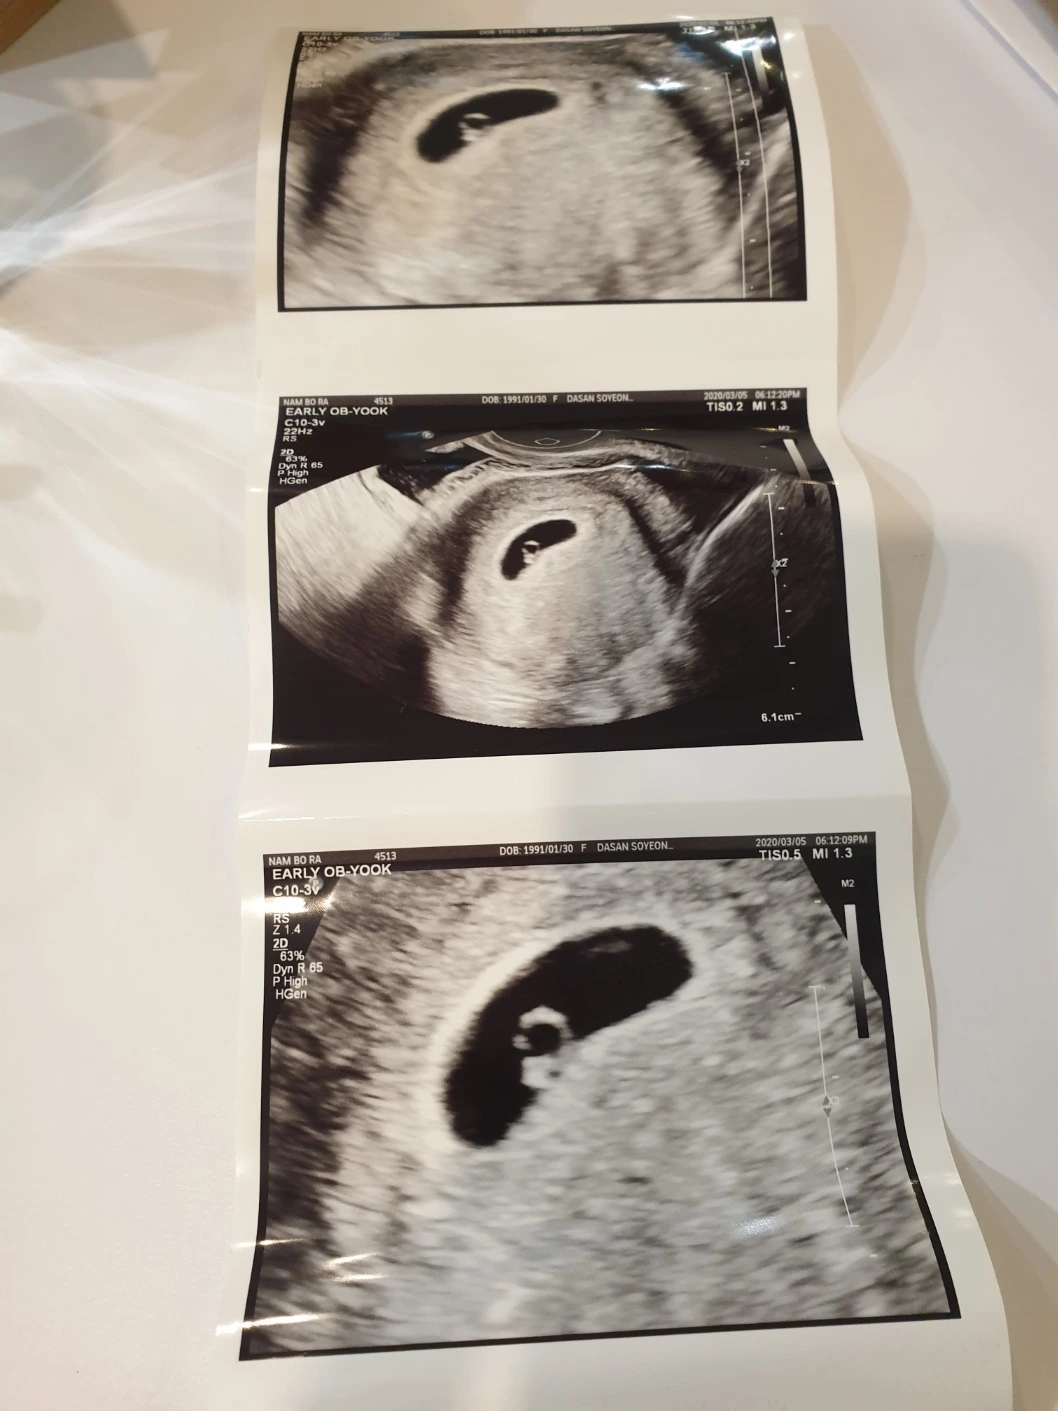

신혼생활 100일 만에 찾아온 축복 같은 소식 한 켠으로 아빠가 된다는 걱정과 부담감이 동시에 찾아왔다. 늘 좋은 아빠가 되는 것이 꿈이었지만 어떻게 해야 할지 전혀 몰랐으니 말이다. 무엇보다 코로나 기간이라 혹시라도 아이가 잘못되면 어떡하지 걱정하는 마음이 앞섰다. 산부인과를 다녀온 와이프가 건넨 태아의 사진을 봐도 도무지 내가 아빠가 된다는 것이 실감이 나지 않았다. 아직 남편으로써 소임을 제대로 다하고 있는지도 모르겠고 변변한 재산이 있거나 사회적 커리어가 월등한 것도 아닌 소시민에 불과한데 내가 과연 자식을 잘 길러낼수 있을까라는 두려움이 몰려왔다. 임신 소식을 접한 지 1주일 정도가 지나자 서서히 현실에 대한 자각이 뚜렷해지기 시작했고 단 하나의 결심으로 모든 자질구레한 생각을 정리했다.